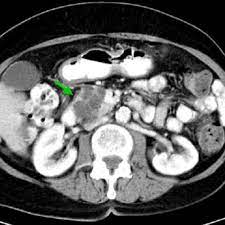

Figure 2 From Benign Multicystic Peritoneal Mesothelioma A Case Report Semantic Scholar

Figure 2 From Benign Multicystic Peritoneal Mesothelioma A Case Report Semantic Scholar from d3i71xaburhd42.cloudfront.net